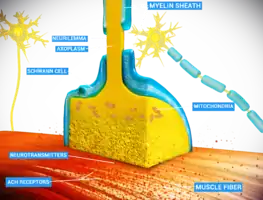

Detailed view of a neuromuscular junction: | |

A neuromuscular junction (or myoneural junction) is a chemical synapse between a motor neuron and a muscle fiber.[1]

It allows the motor neuron to transmit a signal to the muscle fiber, causing muscle contraction.

Muscles require innervation to function—and even just to maintain muscle tone, avoiding atrophy. In the neuromuscular system, nerves from the central nervous system and the peripheral nervous system are linked and work together with muscles.[2] Synaptic transmission at the neuromuscular junction begins when an action potential reaches the presynaptic terminal of a motor neuron, which activates voltage-gated calcium channels to allow calcium ions to enter the neuron. Calcium ions bind to sensor proteins (synaptotagmins) on synaptic vesicles, triggering vesicle fusion with the cell membrane and subsequent neurotransmitter release from the motor neuron into the synaptic cleft. In vertebrates, motor neurons release acetylcholine (ACh), a small molecule neurotransmitter, which diffuses across the synaptic cleft and binds to nicotinic acetylcholine receptors (nAChRs) on the cell membrane of the muscle fiber, also known as the sarcolemma. nAChRs are ionotropic receptors, meaning they serve as ligand-gated ion channels. The binding of ACh to the receptor can depolarize the muscle fiber, causing a cascade that eventually results in muscle contraction.

At the neuromuscular junction presynaptic motor axons terminate 30 nanometers from the cell membrane or sarcolemma of a muscle fiber. The sarcolemma at the junction has invaginations called postjunctional folds, which increase its surface area facing the synaptic cleft.[3] These postjunctional folds form the motor endplate, which is studded with nicotinic acetylcholine receptors (nAChRs) at a density of 10,000 receptors/µm2.[4] The presynaptic axons terminate in bulges called terminal boutons (or presynaptic terminals) that project toward the postjunctional folds of the sarcolemma. In the frog each motor nerve terminal contains about 300,000 vesicles, with an average diameter of 0.05 micrometers. The vesicles contain acetylcholine. Some of these vesicles are gathered into groups of fifty, positioned at active zones close to the nerve membrane. Active zones are about 1 micrometer apart. The 30 nanometer cleft between nerve ending and endplate contains a meshwork of acetylcholinesterase (AChE) at a density of 2,600 enzyme molecules/µm2, held in place by the structural proteins dystrophin and rapsyn. Also present is the receptor tyrosine kinase protein MuSK, a signaling protein involved in the development of the neuromuscular junction, which is also held in place by rapsyn.[3]

About once every second in a resting junction randomly one of the synaptic vesicles fuses with the presynaptic neuron's cell membrane in a process mediated by SNARE proteins. Fusion results in the emptying of the vesicle's contents of 7000–10,000 acetylcholine molecules into the synaptic cleft, a process known as exocytosis.[5] Consequently, exocytosis releases acetylcholine in packets that are called quanta. The acetylcholine quantum diffuses through the acetylcholinesterase meshwork, where the high local transmitter concentration occupies all of the binding sites on the enzyme in its path. The acetylcholine that reaches the endplate activates ~2,000 acetylcholine receptors, opening their ion channels which permits sodium ions to move into the endplate producing a depolarization of ~0.5 mV known as a miniature endplate potential (MEPP). By the time the acetylcholine is released from the receptors the acetylcholinesterase has destroyed its bound ACh, which takes about ~0.16 ms, and hence is available to destroy the ACh released from the receptors.

When the motor nerve is stimulated there is a delay of only 0.5 to 0.8 msec between the arrival of the nerve impulse in the motor nerve terminals and the first response of the endplate [6] The arrival of the motor nerve action potential at the presynaptic neuron terminal opens voltage-dependent calcium channels and Ca2+ ions flow from the extracellular fluid into the presynaptic neuron's cytosol. This influx of Ca2+ causes several hundred neurotransmitter-containing vesicles to fuse with the presynaptic neuron's cell membrane through SNARE proteins to release their acetylcholine quanta by exocytosis. The endplate depolarization by the released acetylcholine is called an endplate potential (EPP). The EPP is accomplished when ACh binds the nicotinic acetylcholine receptors (nAChR) at the motor end plate, and causes an influx of sodium ions. This influx of sodium ions generates the EPP (depolarization), and triggers an action potential that travels along the sarcolemma and into the muscle fiber via the T-tubules (transverse tubules) by means of voltage-gated sodium channels.[7] The conduction of action potentials along the T-tubules stimulates the opening of voltage-gated Ca2+ channels which are mechanically coupled to Ca2+ release channels in the sarcoplasmic reticulum.[8] The Ca2+ then diffuses out of the sarcoplasmic reticulum to the myofibrils so it can stimulate contraction. The endplate potential is thus responsible for setting up an action potential in the muscle fiber which triggers muscle contraction. The transmission from nerve to muscle is so rapid because each quantum of acetylcholine reaches the endplate in millimolar concentrations, high enough to combine with a receptor with a low affinity, which then swiftly releases the bound transmitter.